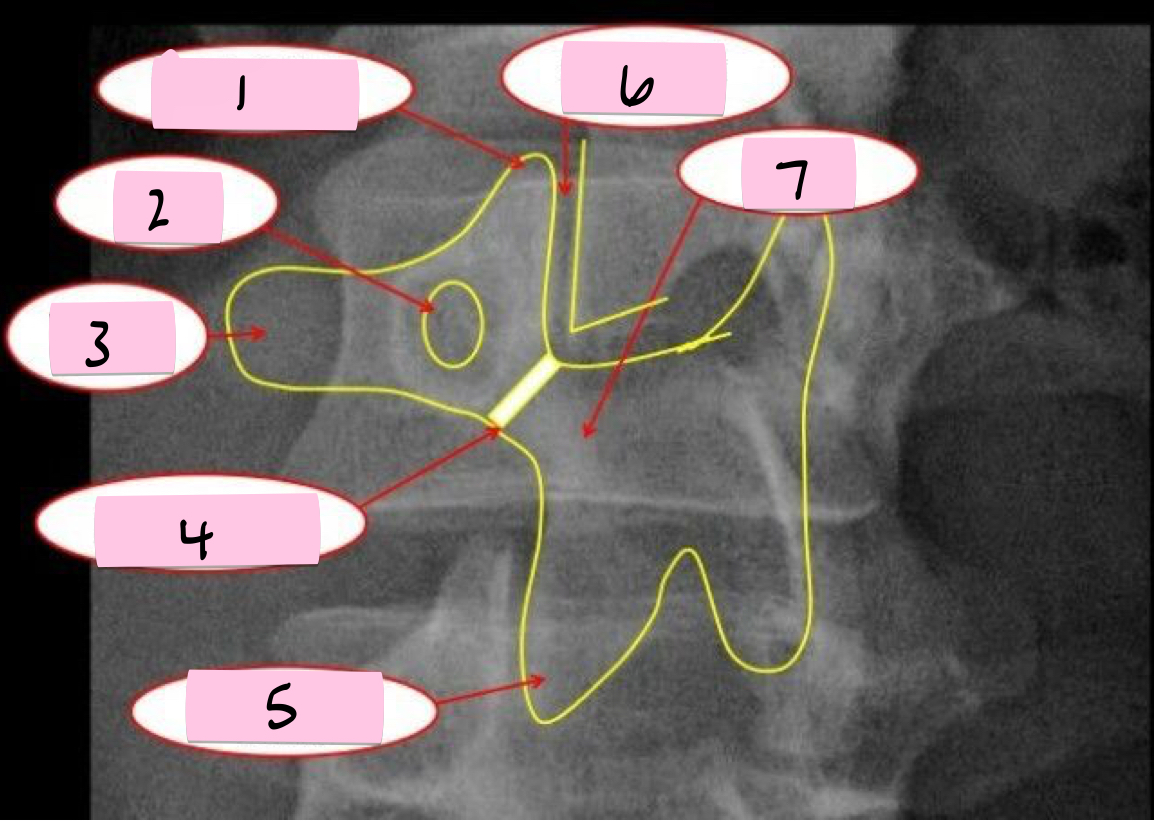

What is 1 pointing to?

Superior articular process

What is 2 pointing to?

Zygapophyseal joint

What is 3 pointing to?

Transverse process

What is 4 pointing to?

Pars interarticularis

What is 5 pointing to?

Inferior articular process

What is 6 pointing to?

Pedicle

What is 7 pointing to?

Scotty dog